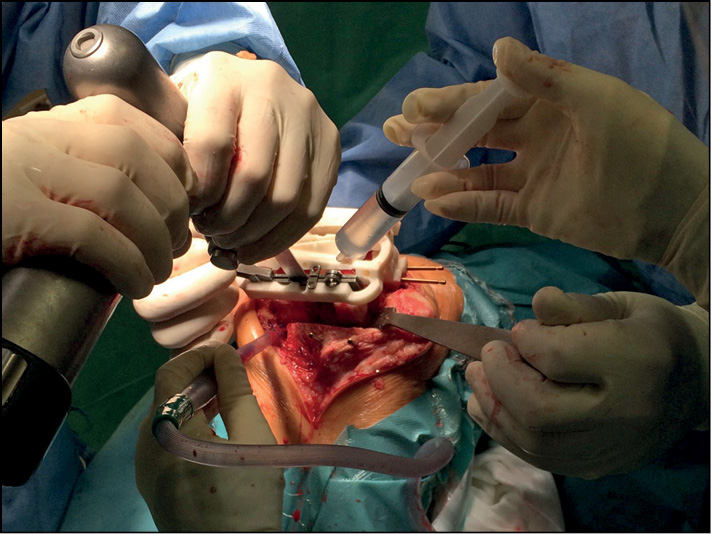

Во время выполнения хирургического лечения, после поднадкостничного выделения мыщелков бедренной и большеберцовой костей, устанавливается первый индивидуальный резекционный блок. Внутренняя поверхность индивидуального резекционного блока полностью повторяет костно-хрящевые анатомические особенности больного, что исключает смещение и погрешности при его фиксации к мыщелку бедренной кости. После фиксации пинами индивидуального резекционного блока в первую прорезь устанавливается запатентованный инструмент — направитель лезвия пилы — и выполняется первый дистальный опил (рис. 2).

Рис. 2. Выполнение дистального опила мыщелков бедренной кости.

Fig. 2. Performing a distal cut of the femoral condyles.